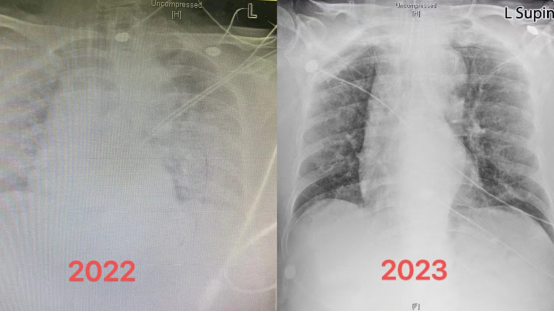

“您看,白肺并不可怕。经过规范治疗都会好转。咱们开始康复锻炼为脱(呼吸)机做准备!”重症医学科副主任赵慧颖举着两张胸片不断鼓励着兴奋地正在康复治疗中的刘奶奶。

“谢谢你们!谢谢你们!”70岁的刘奶奶(化名)不停地重复着这句话,她用最质朴的方式真诚地表达对医护人员的感谢。经过10多天的治疗,“白肺”的刘奶奶已经拔管脱机啦!

刘奶奶被转到重症医学科时,胸闷、呼吸困难、血氧饱和度极低,严重缺氧,肺部影像呈现满满的白色状态,就是俗称的“白肺”。

重症医学科副主任赵慧颖解释道,“白肺”不是新冠病毒感染导致的症状,而是重症肺炎在X光检查下的表现。健康的肺是由通气功能正常的肺泡组成,这样的肺泡充满了空气,在 X 光和 CT 上都是透光的,并且显示为“黑色”。但如果肺部被炎症所广泛浸润,肺里的密度增高,透光性变差,这时在 X 光和 CT 上就表现为一种烟雾笼罩的“白色”。

刘奶奶肺部双侧病变90%以上,无法自主呼吸,氧饱和度不到70%,从急诊转到重症医学科后,立刻进行气管插管,保护性肺通气,并相应给予抗病毒治疗、低剂量激素抗炎治疗、循环管理等规范治疗,尽可能地保护器官储备功能,为患者恢复自身力量抵抗疾病争取时间。

“刘奶奶的康复,对于我们来说也是一种鼓舞,即使是这么严重的‘白肺’,在规范恰当的治疗下也是能康复的。以后会有越来越多的重症患者康复!”赵慧颖表示。